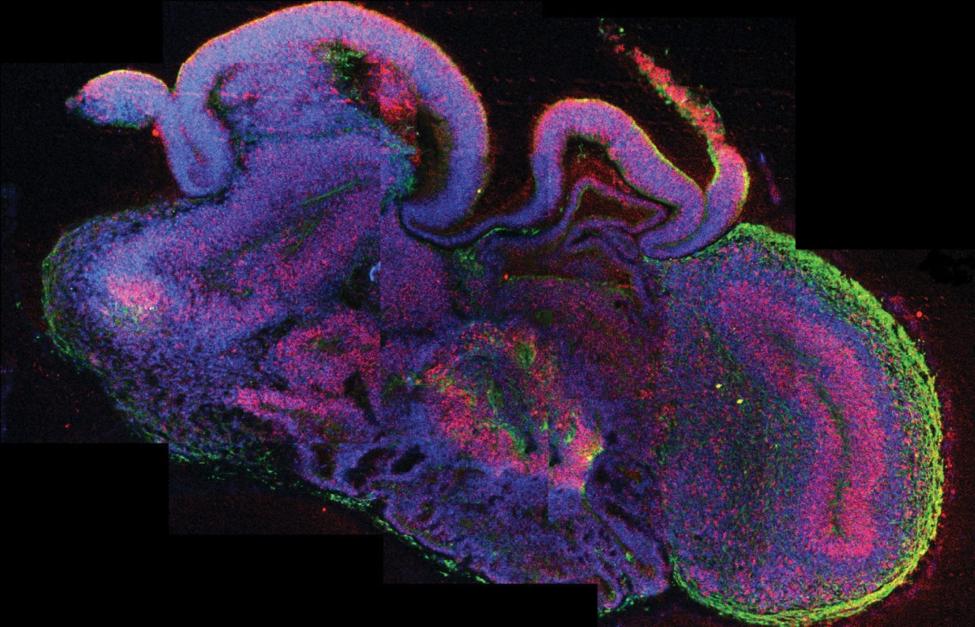

САНКТ-ПЕТЕРБУРГ, 7 июля. /ИТАР-ТАСС/. Специалисты Института мозга человека РАН имени Н.П.Бехтеревой (Санкт-Петербург) научились определять излечимые коматозные состояния. В основе метода лежит сравнение данных, полученных при магнитно-резонанской томографии (МРТ) и позитронно-эмиссионной томографии (ПЭТ), сообщил журналистам директор института Святослав Медведев.

По его словам, если выводы по результатам обоих методов одинаково указывают на поражение одних и тех же зон мозга, и очаги поражения большие, то вернуть такому пациенту сознание невозможно. Несовпадение пораженных зон по итогам исследований МРТ и ПЭТ дает надежду на выздоровление, говорит он.

"Сочетание большого и небольшого очагов говорит о том, что нейроны мозга "впали в спячку", и человека можно вылечить", - пояснил он и добавил, что такое явление свойственно человеческому мозгу в экстремальных ситуациях, например, при получении серьезной травмы.

Медведев отметил, что человек в состоянии излечимой комы испытывает сильнейший спазм, и весь потенциал его нейронов расходуется только на контроль за состоянием тела. Основу лечения таких пациентов составляют внутримышечные инъекции ксеомина – препарата, широко применяемого в косметологии для разглаживания мимических морщин и больше известного как ботокс. "Мышцы постепенно расслабляются, и к человеку возвращается сознание", - сказал Медведев.